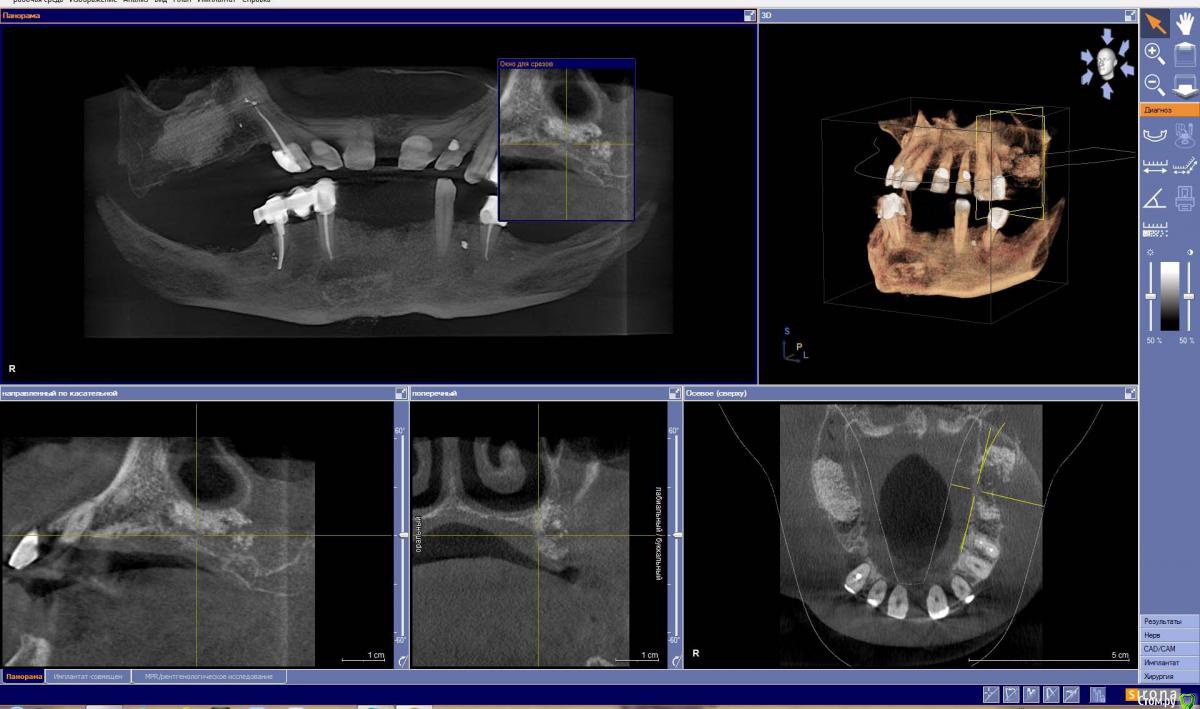

Larnary Опубликовано 1 февраля, 2015 Автор Поделиться Опубликовано 1 февраля, 2015 (изменено) графта насыпано на полляма деревянных. с учетом суммы и статуса линики премиум класса,то предполагаю,что био осс. но уточню.и что за клиника-тоже спрошу. Если делать верх импланты, то хватает ли графта слева? Изменено 1 февраля, 2015 пользователем Larnary Ссылка на комментарий

carloss Опубликовано 1 февраля, 2015 Поделиться Опубликовано 1 февраля, 2015 графта насыпано на полляма деревянных. с учетом суммы и статуса линики премиум класса,то предполагаю,что био осс. но уточню.и что за клиника-тоже спрошу. Если делать верх импланты, то хватает ли графта слева?там где низко, можно использовать короткие.. думаю 8-9мм есть везде.. бухты конечно местами оставили, медиально, но если туда не будут торчать импланты, то всё должно быть ок.. а так покатайте КТ хорошенько, померяйте 1 Ссылка на комментарий

Larnary Опубликовано 1 февраля, 2015 Автор Поделиться Опубликовано 1 февраля, 2015 вот и мне кажется,что маловато. предполагаю,сверху обойтись 6-ю имплантами-по 3 с каждой стороны Ссылка на комментарий

колесников Опубликовано 1 февраля, 2015 Поделиться Опубликовано 1 февраля, 2015 (изменено) значит отвечу по пунктам. к съемному пациент готов,тк его ориентировали к съемнику на имплантах. съемник носил-видно по замку на премоляре низ справа. срасстаться с зубами готов,но скрипя зубами.работать привык по классике. съемников на имплантах в моей практике было мало. имплантолог у меня опытный,пластику делает. с розовой десной на протезе знаком конечно. системы у нас в клинике Semados и Misкое что прояснилось. я думаю внизу съёмник стоит оставить. пациент привык ,а у нас тут приличное межальвеолярное . делать ли бюгель или съёмный на имплатах-это детали. внимание на верх. фронт хоть и крепкий но имеет место клиническое выдвижение и приличные диастемы. их либо собирать ортодонтически либо распрощаться с ними. меня смущает область синуслифтинга справа. по виду это интегрированый био-ос. это самый плохой вариант интегрированого материала. примерно 1го типа и абсолютно не васкуляризированый. имел неприятный опыт работы с такой костью. интеграции имплантата не произойдёт. что делать? можно попробовать сформировать ложе под имплант и оставить на месяц-полтора,а после установить имплант. либо обойти эту зону. слева ещё хуже-там прорастание эпителия между гранул материала. опять же либо не трогать либо повторная пластика.... короче надо прикинуть на артикуляторе,покрутиь кт. подумать ,посчитать. но всегда остаётся 4 импланта во фронте и балка Изменено 1 февраля, 2015 пользователем колесников 1 Ссылка на комментарий